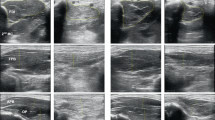

Six participants with incomplete SCI underwent US imaging and MRI of their gastrocnemius and tibialis anterior (TA) muscles.

Significant correlations were found between US muscle thickness and MRI CSA in the gastrocnemius (R=0.91, P<0.001), and TA muscles (R=0.58, P<0.05). US muscle thickness in the gastrocnemius and TA of patients with incomplete SCI may be used as a cheaper alternative measure of CSA as measured using MRI, and this measure may be clinically useful to track progress in muscle gains during rehabilitation.